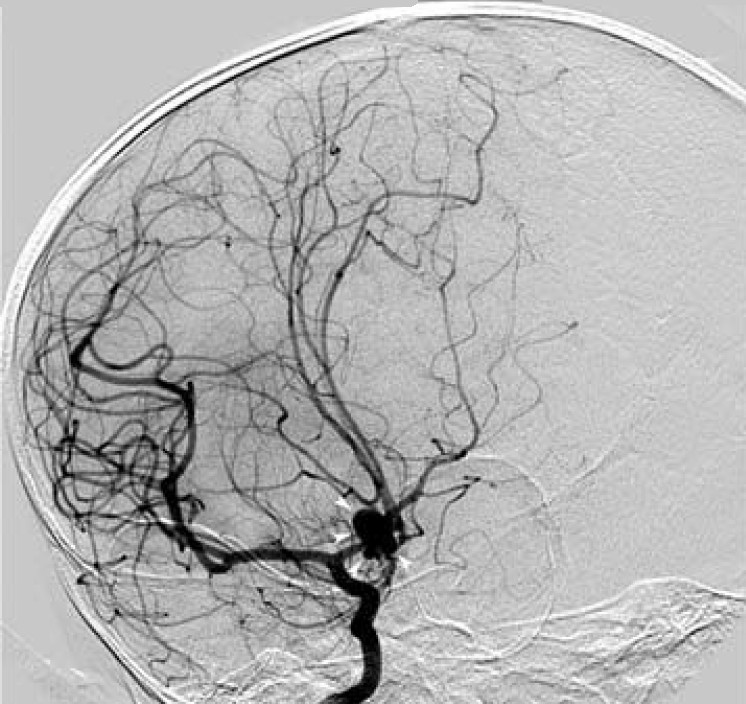

De diagnose wordt gesteld op het arteriogram waarbij focale

of segmentale vernauwingen of occlusie zichtbaar zijn in de aorta of directe

aftakkingen of de grote arteriën van de extremiteiten, niet verklaard door andere

oorzaken zoals atherosclerose. In Japanse definities wordt het criterium jonger

![Takayasu arteritis (click on photo to enlarge) [source: Justin Ly - Wikimedia - Creative Commons License 1.0 - Public Domain Image] Takayasu arteritis](../../../images/Takayasu-arteritis-2z.jpg) |

Takayasu

arteritis |

Röntgenfoto's: Justin Ly en Weiss PF. et al. - Wikimedia (Creative

Commons License

1.0

/

2.0).